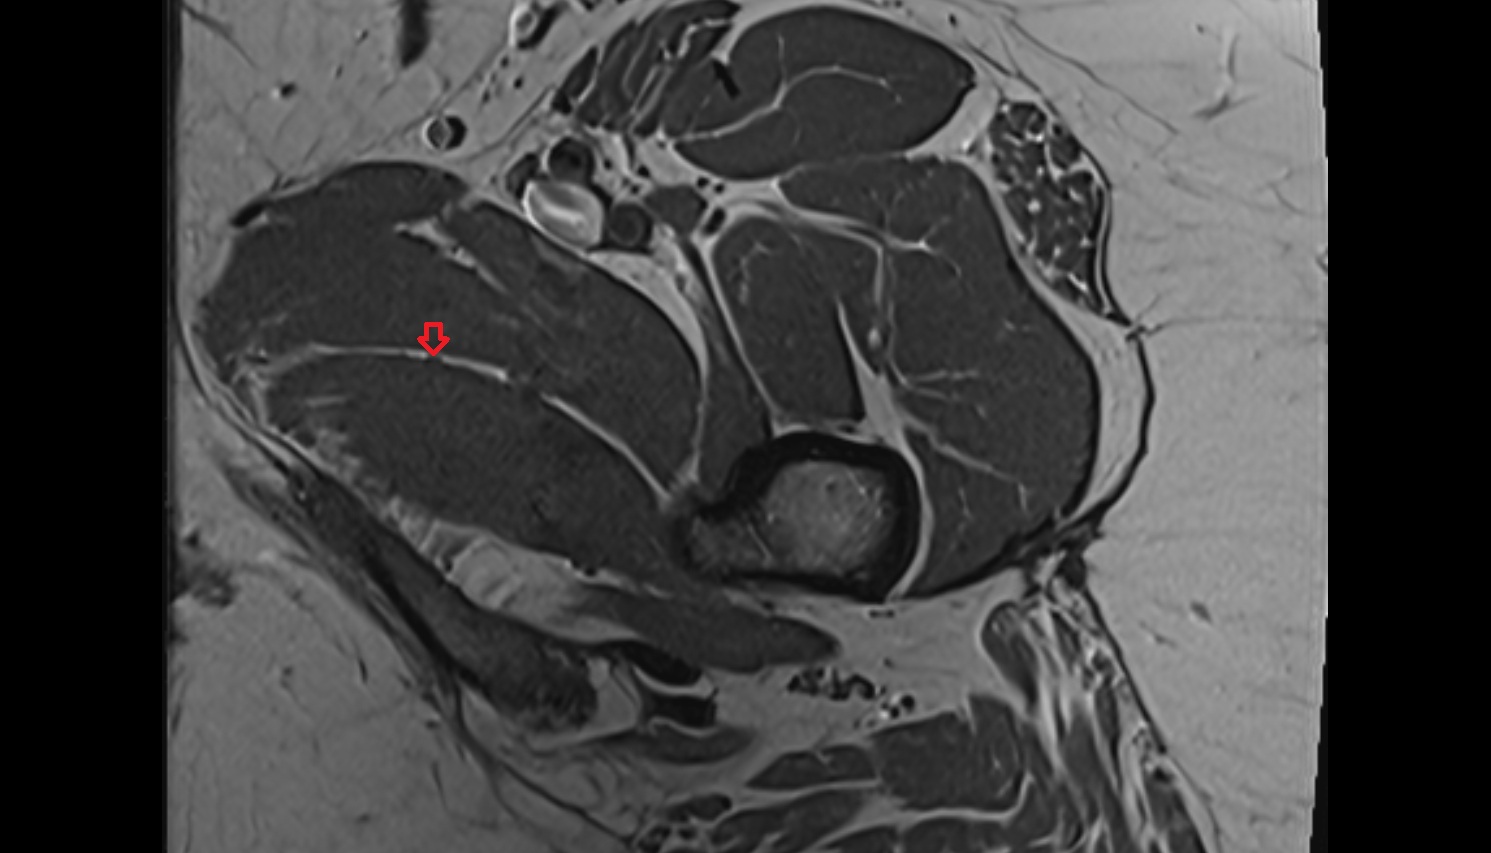

- Heart

- Left ventricle

- Right atrium

- Left atrium

- Right ventricle

- Interventricular Septum

- Left atrioventricular valve (mitral or bicuspid valve)

- Right atrioventricular valve (tricuspid valve)